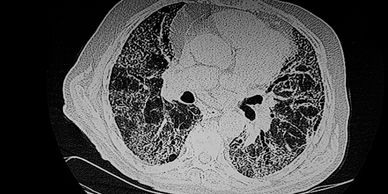

Enfermedad pulmonar intersticial

El intersticio pulmonar es el tejido que rodea los sacos de aire (alveolos) en los pulmones, actuando como un marco de soporte para matener su estructura y funcionamiento como el intercambio de oxigeno cuando este se daña por inflamación o cicatrices o fibrosis causa solo falta de aire, y con el tiempo aumenta sin que el paciente se de cuenta.